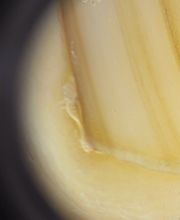

Il medico specialista Dr. Pier Alessandro Fanti opera nel settore della dermatologia e anatomia patologica, il dottore oltre a queste specializzazioni si occupa anche di malattie veneree. Il medico specialista Dr. Pier Alessandro Fanti è il dirigente medico dell'unità operativa dermatologia del Policlinico Sant'Orsola Malpighi. Il dermatologo presta la massima attenzione ai suoi pazienti garantendo esperienza nel settore e ladeguata competenza nella soluzione di problematiche e patologie varie. Il Dr. Fanti si occupa di patologia annessi cutanei, chirurgia microscopicamente controllata, dermatologia oncologica, ma anche di terapie e trattamenti per la chirurgia unità ungueale, crioterapia e trattamenti laser CO2.